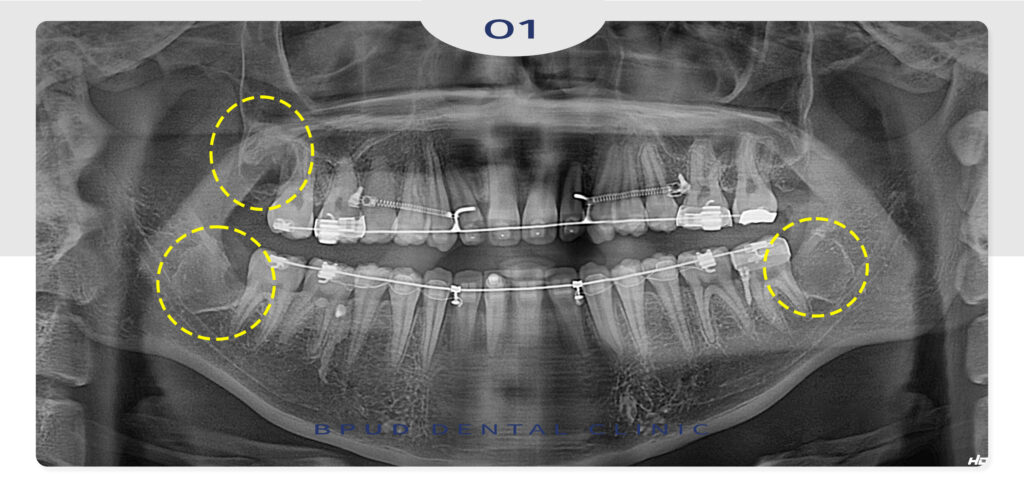

일반적으로는 파노라마 엑스레이로 전체 위치를

확인한 뒤, CT 촬영을 통해 신경과 뿌리,

인접 치아와의 거리를 입체적으로 분석해

위험도를 분류하게 됩니다.

오늘은 매복되어 있는 사랑니 3개를

동시에 발치하신 학생 환자분을 소개해

드리도록 하겠습니다.

현재 대학병원에서 교정을 진행 중인 분으로

완전 매복 사랑니 발치가 필요하여

의뢰서를 가지고 인터넷에서 부평수면치과를

검색하여 내원해 주셨습니다.

환자분께서는 완전히 잇몸 속에 매복되어 있는

사랑니와 치근단 형성이 안되어 있어

난이도가 매우 높은 케이스였으나,

환자분의 요청으로 인하여 하루에 3개 사랑니를

발치 진행하기로 하였는데요.

3D CT 촬영을 통해 정밀한 검진 후

환자분과 보호자분 모두 한번에 발치를

원한다고 하셨고, 거주하시는 곳이 멀어

모두 한번에 발치를 진행하기로 하였습니다.